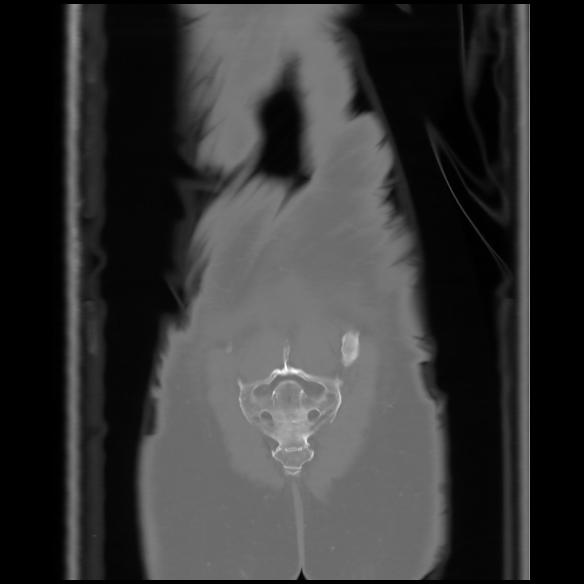

6 CUERPO,CE,Coronal,3.000,CUERPO,Coronal,